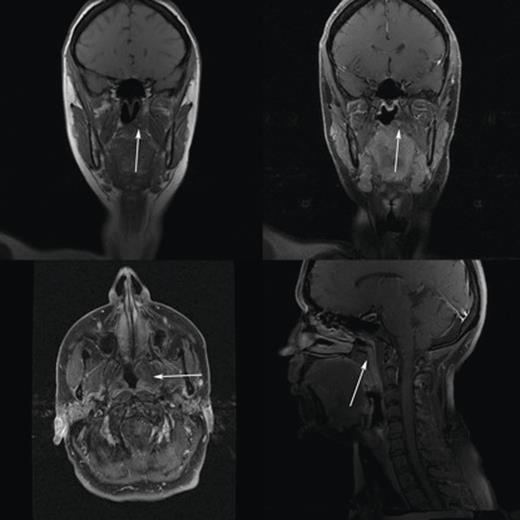

A left grommet was inserted and the lesion was biopsied, revealing an amyloid plaque confirmed on Congo Red staining. Computed tomography and magnetic resonance imaging scans were subsequently performed (see Figs 2 and 3) which showed a ‘1.5 × 2.3 cm mass arising from the torus tubaris and pterygoid fossa, protruding into the post nasal space’. Further radiological investigations of the entire body were conducted for investigation primary amyloidosis which all proved negative, confirming the diagnosis of primary isolated sinonasal amyloidosis. Management options were discussed and, due to the resolution of symptoms, a period of watchful waiting was commenced. Two years after initial presentation, the patient was discharged back to her GP without need for further intervention.